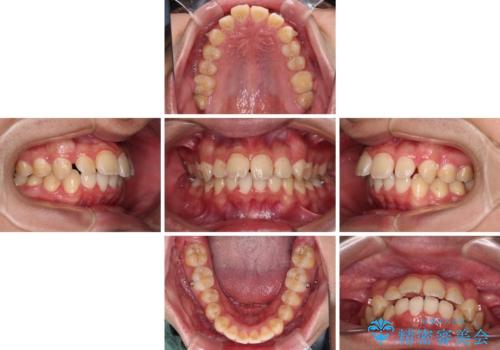

- 深く咬みこんだ前歯と、それに伴い前方に突出した上顎前歯を気にして来院された患者様です。

下顎の歯列は、奥歯が前方に傾斜し、前歯が上顎の歯の付け根に食い込むように内側に傾斜していました。

また、左右の犬歯の位置関係は上顎歯列が前方に位置する咬み合わせとなっており、インビザライン単体で治療するよりは、ワイヤー装置や補助装置を併用した方がより良い仕上がりになることが期待されました。

インビザラインで難儀する部分をワイヤー装置にて確実に改善しておくことで、インビザラインのみで行うよりも治療期間を短縮するとともに、より理想的な歯列に近づけて仕上げることができました。